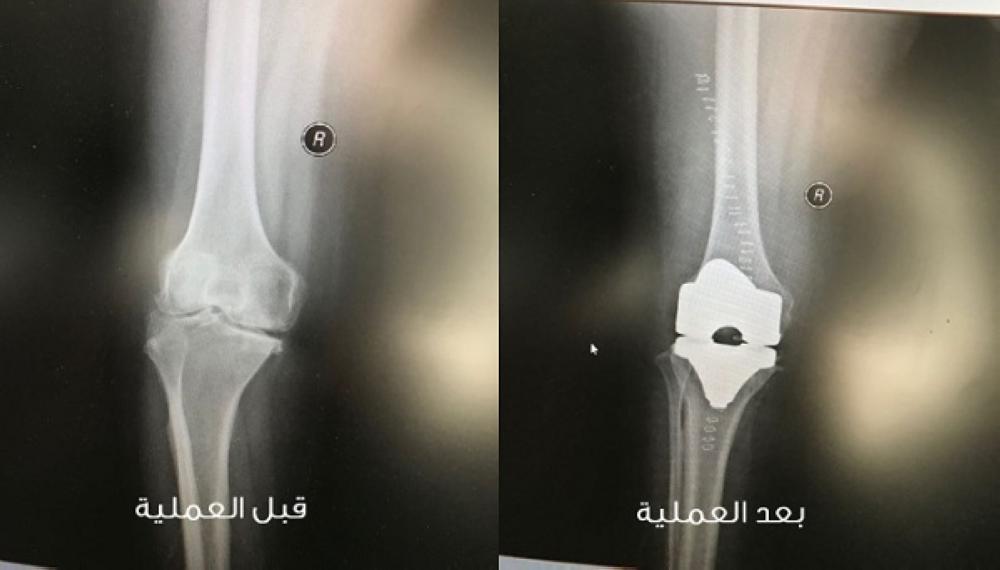

تمكن فريق طبي بمستشفى الأمير متعب بن عبدالعزيز بمدينة سكاكا من استبدال مفصل الركبة لمريضة خمسينية بمفصل أسمنتي، منهياً معاناة سنوات طويلة، إذ كانت تعاني من ألم مزمن بمفصلي الركبتين لعدة سنوات، وتأخرت في إجراء عملية استبدال كلي لمفصل الركبة اليمنى، وبعد إجراء الفحص الطبي، ومعاينة أشعة على الركبتين، قرر الفريق الطبي إجراء عملية استبدال كلي لمفصل الركبة اليمنى لها بمفصل صناعي أسمنتي كامل بمعاونة فريق المفاصل بالمستشفى.

وبعد العملية تمكنت المريضة من السير على قدميها باستخدام الماشية الطبية، لتغادر المريضة المستشفى بحالة طبية مستقرة.

المفصل قبل وبعد العملية